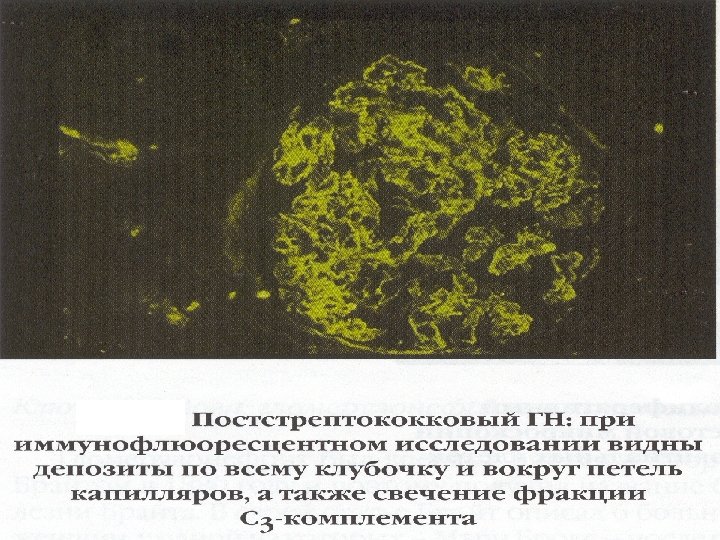

Электронная микроскопия почечного клубочка в норме Постстрептококковый ГН: при электронной микроскопии видны характерные отложения в виде «горбов» на БМК